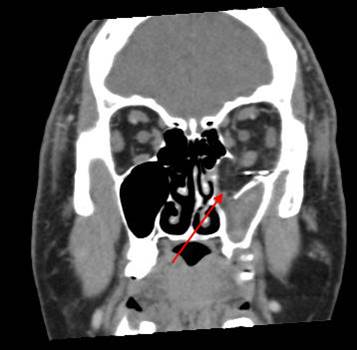

Nasolacrimal Canal and Sac

There is bony injury to the nasolacrimal canal.

The nasolacrimal sac appears to be intact.

The mesial naso-orbito-ethmoid complex is fractured. Specifically, there is bony injury of the nasal bones or the frontal process of the maxilla and the medial walls of the orbit are abnormal.

The intercanthal distance is increased.